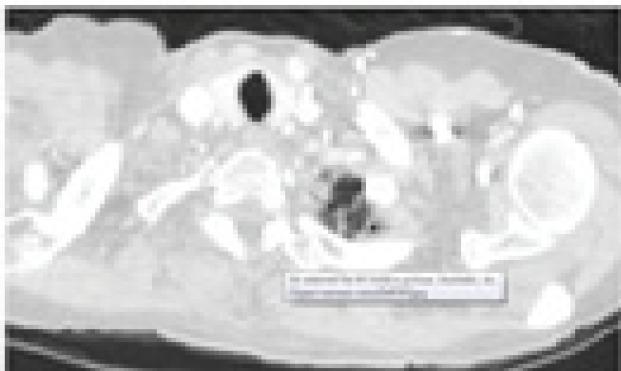

一种用于肺结节分类的新型混合特征提取模型。

A Novel Hybrid Feature Extraction Model for Classification on Pulmonary Nodules.

In this paper an improved Computer Aided Design system can offer a second opinion to radiologists on early diagnosis of pulmonary nodules on CT (Computer Tomography) images. A Deep Convolutional Neural Network (DCNN) method is used for feature extraction and hybridize as combination of Convolutional Neural Network (CNN), Histogram of Oriented Gradient (HOG), Extended Histogram of Oriented Gradients (ExHOG) and Local Binary Pattern (LBP). A combination of shape, texture, scaling, rotation, translation features extracted using HOG, LBP and CNN. The Homogeneous descriptors used to extract the feature of lung images from Lung Image Database Consortium (LIDC) are given to classifiers Support Vector Machine (SVM), K-Nearest Neighbour (KNN), Decision Tree and Random Forest to classify nodules and non-nodules. Experimental results demonstrate the effectiveness of the proposed method in terms of accuracy which gives best result than the competing methods.

摘要